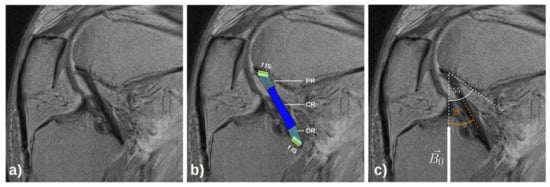

2.4.2. Manual Segmentations and Image Post-Processing